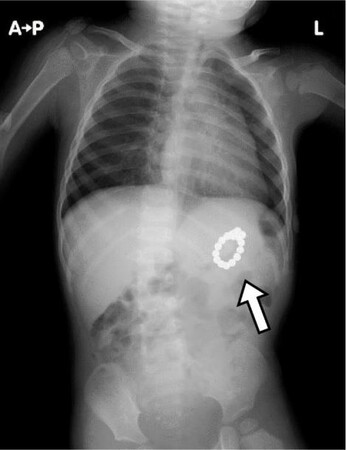

■水で膨らむボール

水で膨らむボールを飲み込むと胃液や腸液等の体液を吸収し、消化管内で膨潤します。狭い 消化管内で詰まった場合には、自然排出されにくく、腸閉塞を生じるおそれがあります。